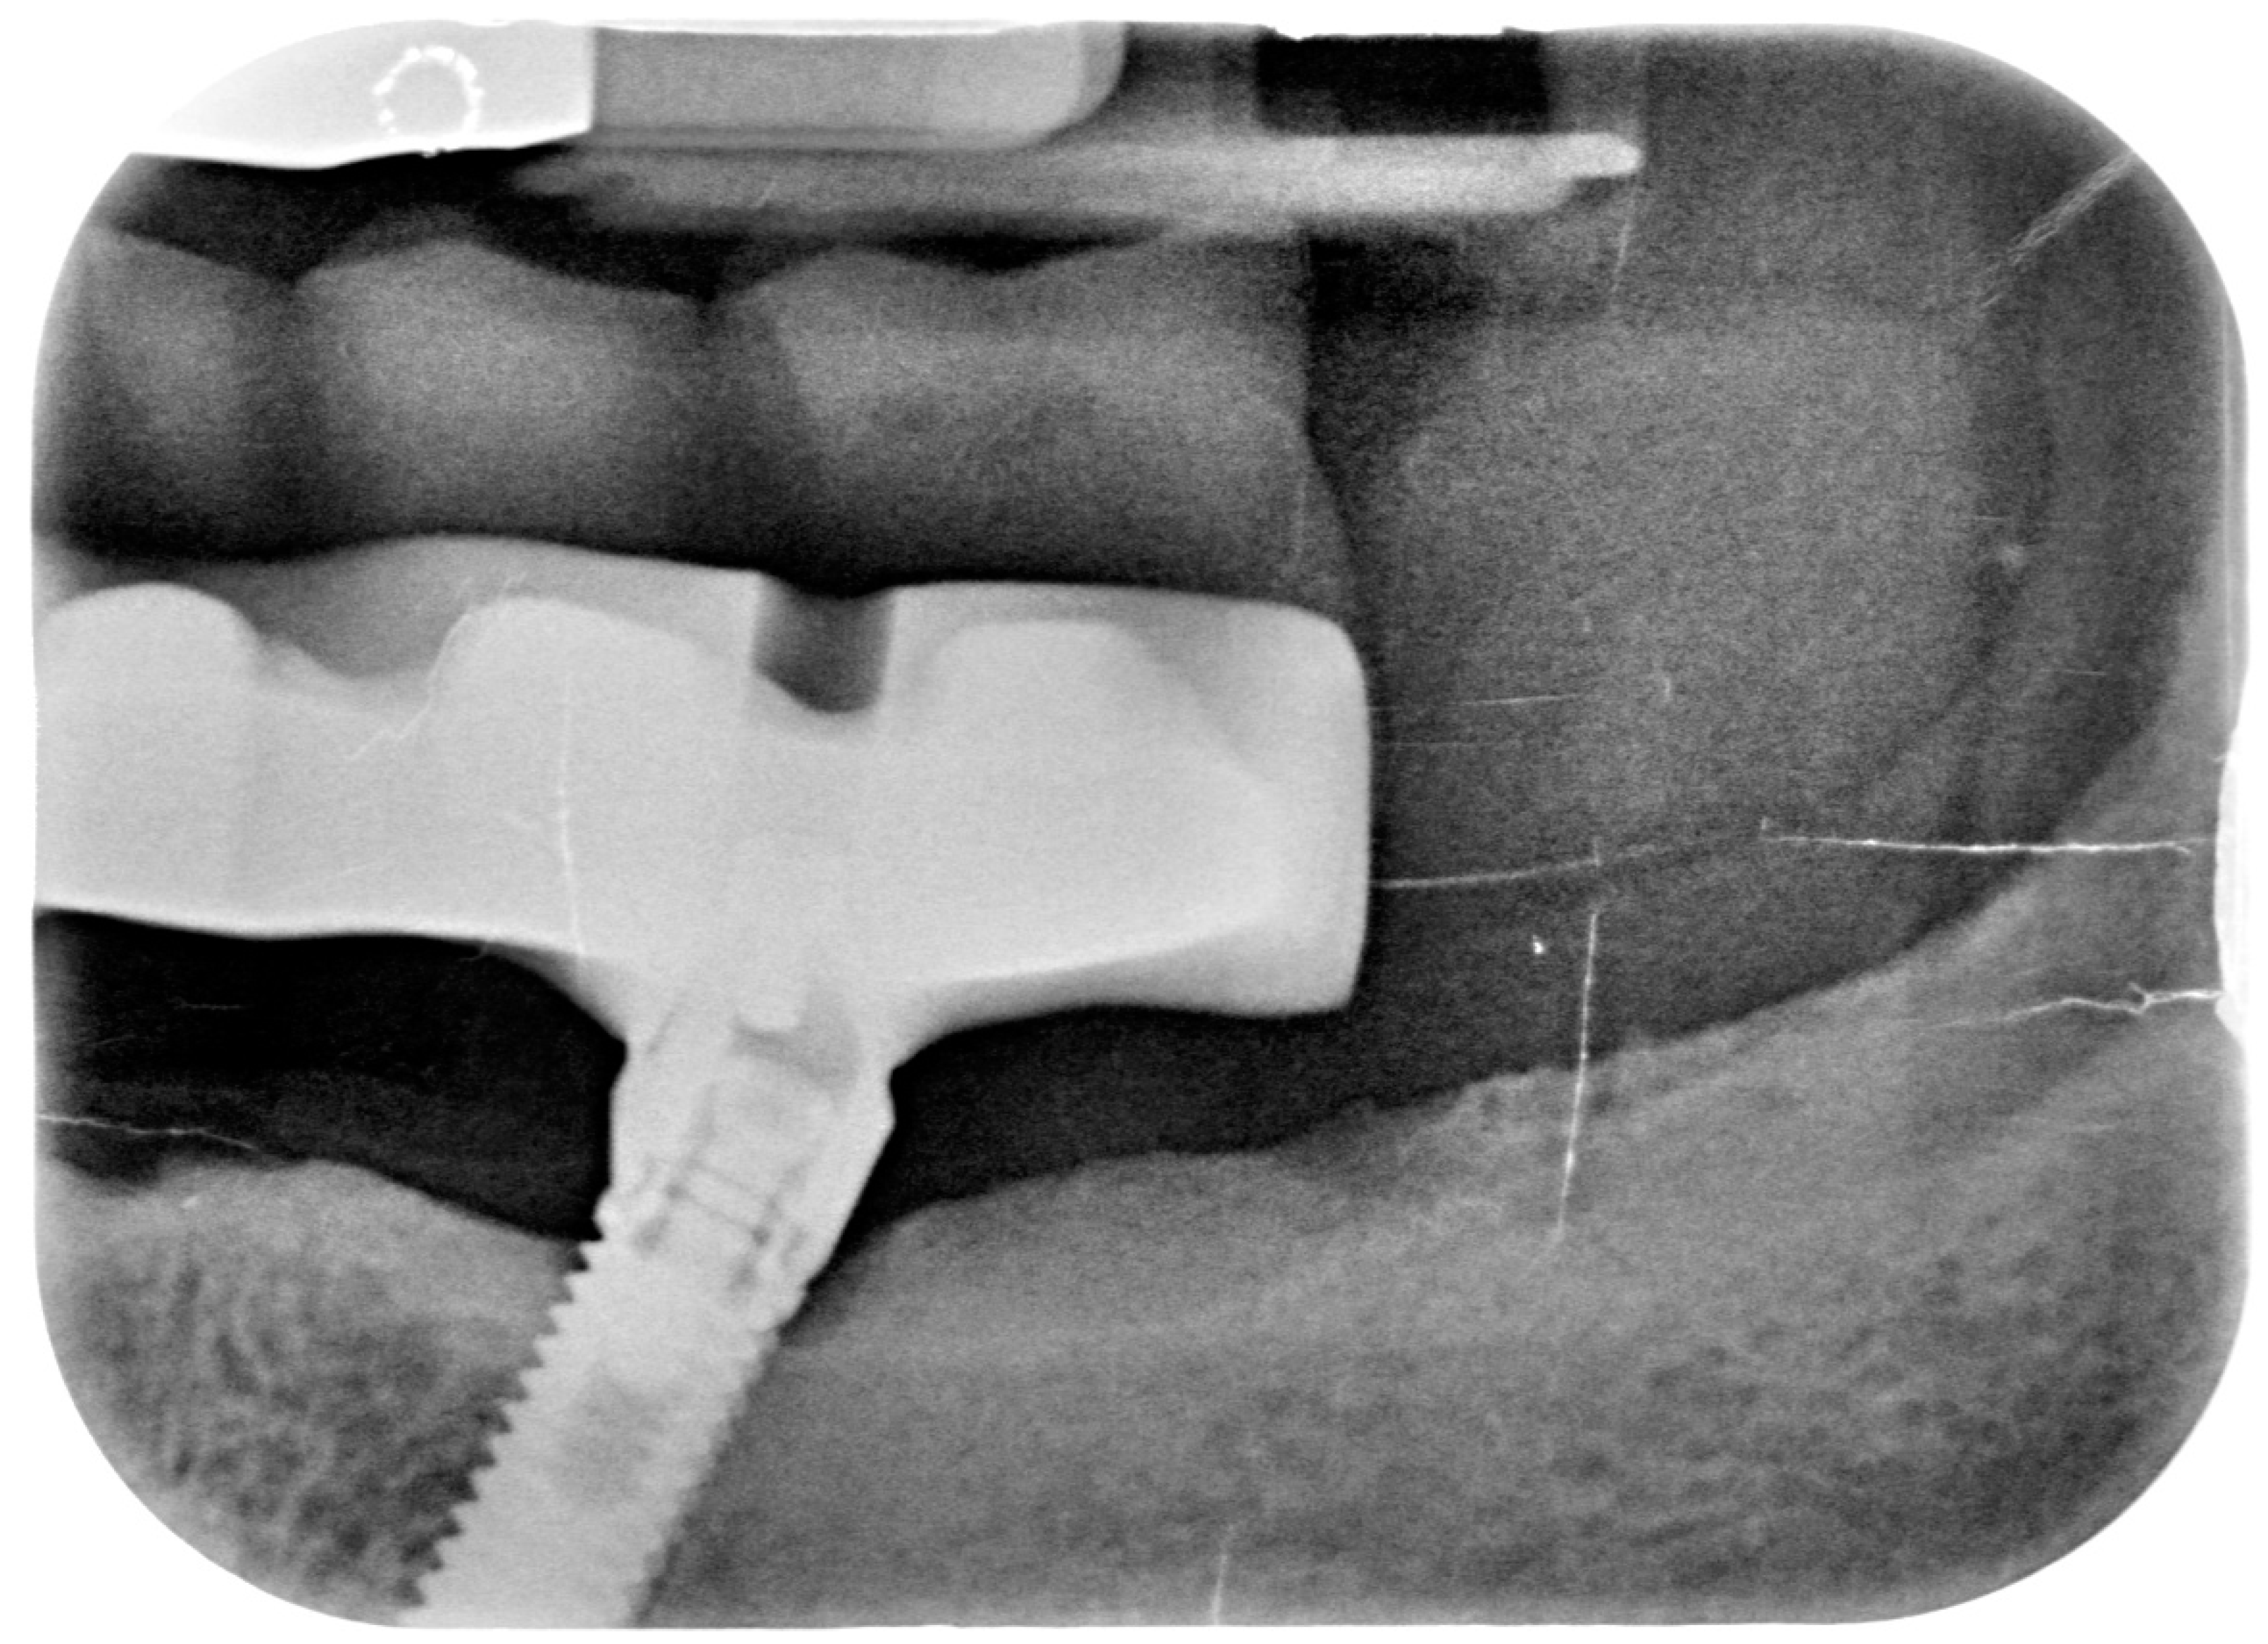

After removing the prosthetic rehabilitations, diagnosis of the soft tissue was done. Peri-implant assessment (PPD, TL, BI, PI, and mobility) and, subsequently, assessment of color, contour, consistency of soft tissues was performed. Individual oral hygiene instructions including re-education and motivation if needed was done. Bidimensional radiographic assessment (with periapical and panoramic radiograph) was performed (Figure 10 and Figure 11).

Figure 10.

X-ray of 3.5 dental implant in patient before treatment.

The clinical assessment allowed finding a probing depth of 6 mm mesial/circumferentially to 3.5 with bleeding in the two lower jaw distal implants and a probing depth of 4–2.5 mm mesial/circumferentially with bleeding in the two lower jaw central implants. In the upper jaw, a probing depth of 1–2 mm was found. None of the implants showed mobility.

A bidimensional radiographic assessment of the lower jaw and upper jaw implants (with periapical and panoramic radiograph) was done. In the lower jaw implants, a concave bone resorption can be observed of about 4 mm mesial and distal to both distal implants (3.5 and 4.5). No bone resorption was revealed on the two lower jaw central implants and on the four implants positioned in the upper jaw.